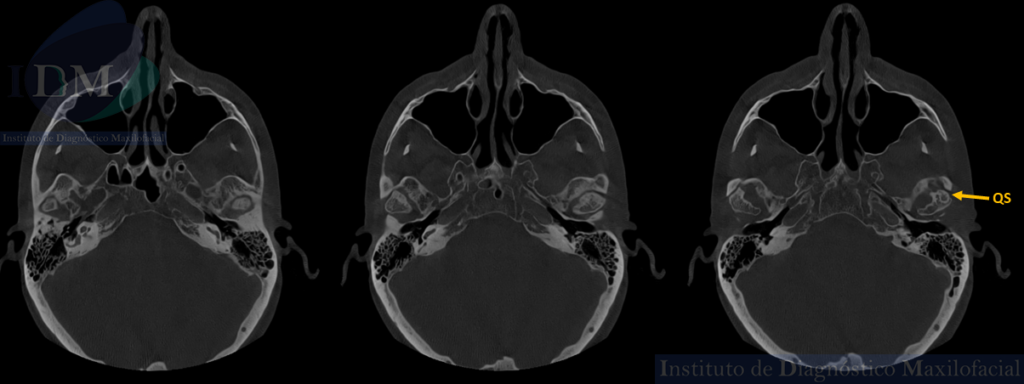

A la ampliación de estudio con tomografía computarizada de haz cónico (TCHC) se revelan hallazgos adicionales como:

- Osteofitos (O), indicativos de crecimiento óseo anómalo en los cóndilos mandibulares.

- Quiste óseo subcondral (QS), alteración en el hueso subcondral que refleja cambios degenerativos en la estructura ósea subyacente.

- Reducción de los espacios interarticulares en ambas articulaciones temporomandibulares, sugiriendo un estrechamiento del espacio articular.

CORTES AXIALES